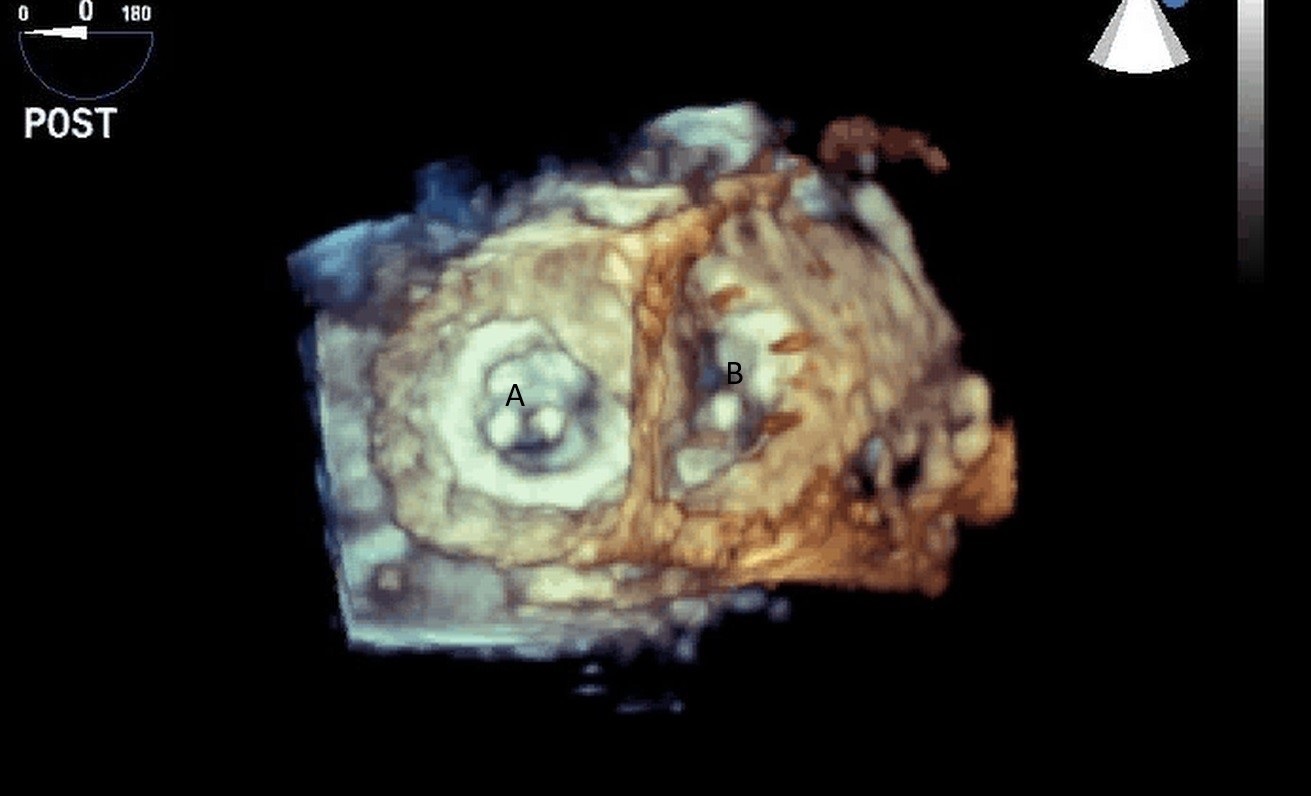

Fig. 9.Real time 3D TEE imaging visualizing the Impella in relation to the aortic valve and LVOT. (A) Impella. (B) Ascending aortic root.

Both TTE and TEE can help with ideal positioning of the Impella (Figs. 5,6). The distance from the aortic valve to the Impella inlet should be measured. This should ideally be 3.5–4 cm for all Impella devices except for the Impella 5.5 for which it is 5 cm [15] (Fig. 7). The outlet should be 1.5–2 cm above the sinuses of Valsalva. The catheter should be angled towards the LV apex and away from the septum and mitral valve. The positioning of both the inlet in the LV cavity and the outlet above the aortic valve should be confirmed. Color flow doppler imaging can help confirm this positioning as a mosaic pattern will be visualized near the inlet and outlet ports on spectral doppler (Fig. 8). Real-time 3D echocardiography can also be used to help in visualizing Impella positioning relative to other anatomical structures (Fig. 9). After placement of the Impella, the aortic and mitral valves should be interrogated for any new or worsening regurgitation or dysfunction [16]. TEE can also help identify additional complications of Impella placement including pericardial effusion or LV free wall rupture [17].